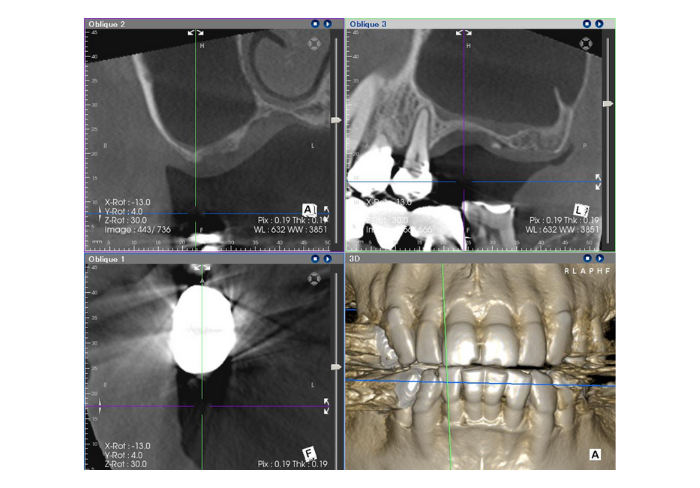

Before

患者の症状:インプラントをしたいが骨がない。

治療方法:上顎洞内への造骨

治療結果:インプラントを入れるのに十分な骨ができた。